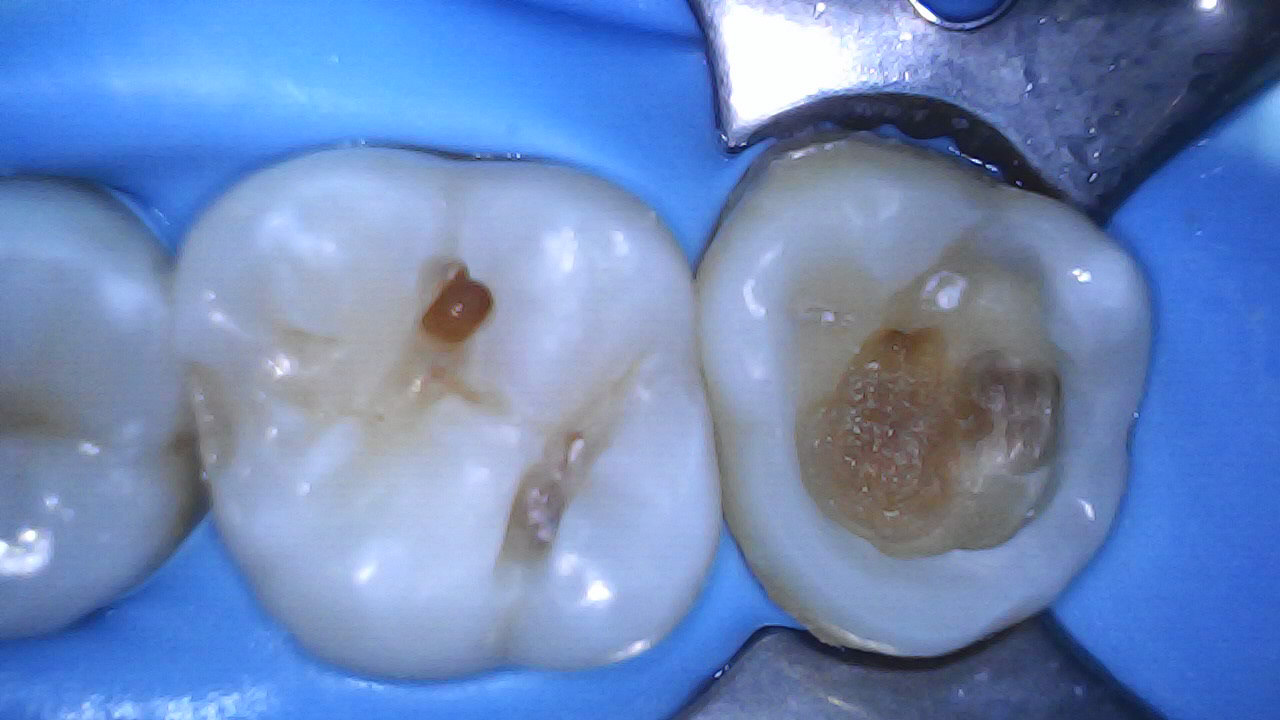

3 months later - Pulp remained vital, tooth asymptomatic (mesial overhang removed)

Temp fuji replacement with Ga-enial injectable A2, Ever X posterior & Filtek XT A2B